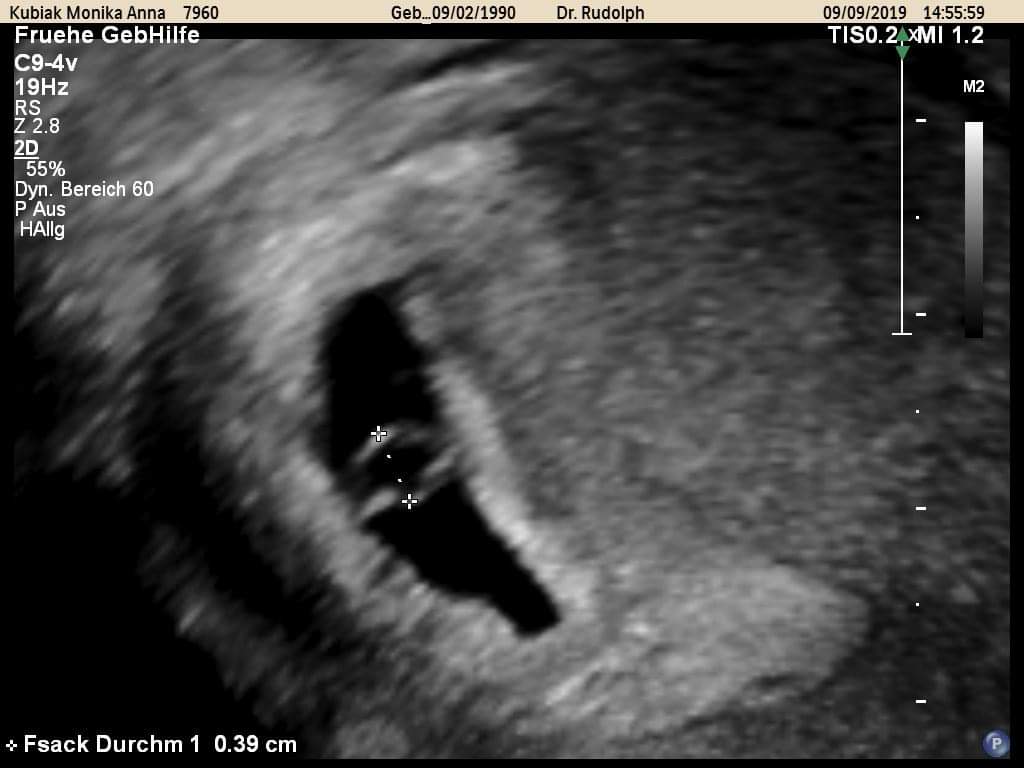

Wyszłam od lekarza z uśmiechem na ustach jest pęcherzyk i ciałko żółte! Wierzę, że w tej ciąży będzie wszystko dobrze ;) Teraz 3 tygodnie zwolnienia do kolejnej wizyty.

To 5t4d.

jeszcze nie-za wcześnie ...W 5.-6. tygodniu we wnętrzu pęcherzyka pojawia się pęcherzyk żółtkowy, który odżywia zarodek, zanim wykształci się łożysko.

w 6. tygodniu ciąży zarodek może jeszcze nie być widoczny w trakcie badania USG ze względu na zbyt małe rozmiary. Echo zarodka można najczęściej uwidocznić po 6. tygodniu trwania ciąży, a około 7. tygodnia - czynność serca płodu.

no a ja bylam w 5+4 i lekarka mowi, no w sumie juz moglby byc widoczny ale nie musi itp i tak niedok9nca byla zadowolona.. ale widze ze prawie u kazdej jest tak, ze nie bylo widac. Ona mowila ze juz widzi ten zloltkowy